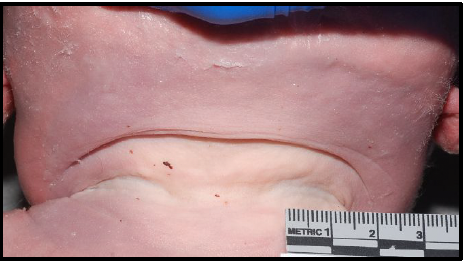

maceration

degenerative changes in fetal tissue when retained in utero